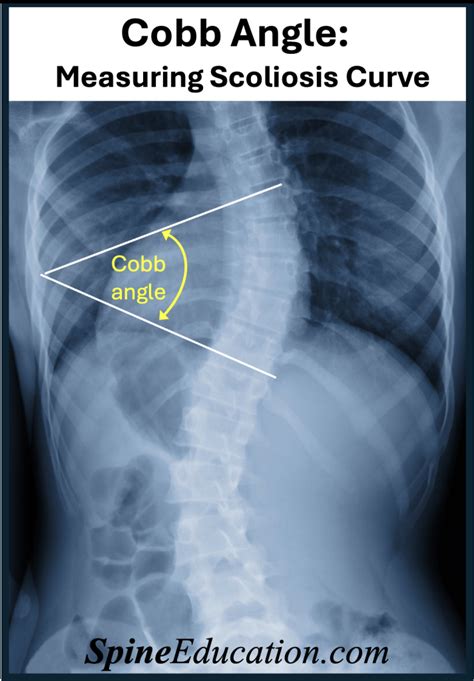

Measuring the Scoliosis Angle: The Cobb Angle Explained

Alright, so when we talk about the scoliosis angle , we’re almost always referring to the Cobb angle . This is the gold standard, the main way doctors measure the severity of the spinal curve in scoliosis. Think of it like this: your spine is supposed to be nice and straight, or have a gentle, natural curve. But with scoliosis, there’s an abnormal sideways curve. The Cobb angle helps us quantify how much it curves. How do they do it? It’s all done using X-rays. The radiologist or your doctor will identify the two most tilted vertebrae at the ends of the main curve. Then, they draw lines along the tops and bottoms of these vertebrae and measure the angle where these lines intersect. Simple, right? Well, conceptually, yes! In practice, it requires a skilled eye and precise measurements, but the principle is straightforward. This angle gives us a numerical value, usually in degrees, that tells us the magnitude of the spinal deviation. It’s crucial because this single number, the Cobb angle, directly influences how scoliosis is classified and, most importantly, how it’s treated. A small angle might mean observation, while a larger angle could necessitate more aggressive interventions. So, understanding the Cobb angle is paramount to grasping the severity and potential impact of scoliosis on an individual’s health and mobility. It’s the objective measurement that guides the entire management strategy, from initial diagnosis to long-term follow-up. This methodical approach ensures consistency and allows for reliable tracking of curve progression over time, which is vital for making timely and appropriate treatment adjustments. The precision of the Cobb angle measurement is key; even a few degrees can make a difference in treatment recommendations, highlighting the importance of accurate interpretation by healthcare professionals.